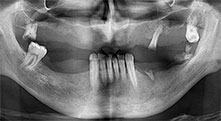

Could you describe briefly, for example, your procedure for mobilizing bone blocks for transplantation?

Bratu: We prefer to harvest bone from the external oblique ridge of the posterior mandible, not from the interforaminal region. After the soft-tissue incision, we use the new saws to define the amount of bone to harvest. With this approach, we also use them for the entire preparation in almost 80% of cases. We may also use other piezo instruments and then at the end a chisel to mobilize the block. We find that this is a very effective surgical technique.